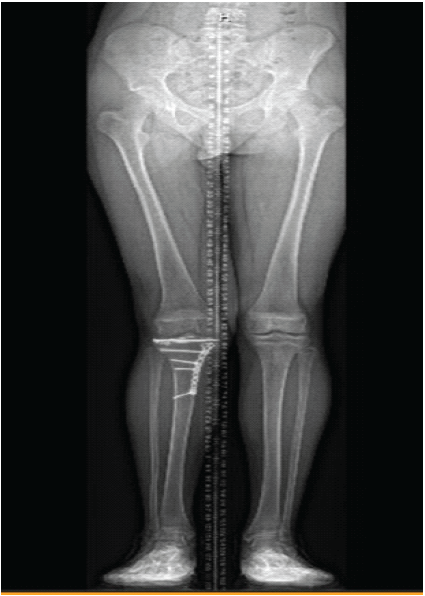

The patient was kept non-weight-bearing for 12 weeks postoperatively with instructions to work on knee range of motion. At 6 weeks post-operative, his range of motion was 15–90° and he was instructed to begin physical therapy. At 4 months post-operative, his range of motion was 5–120° and he was ambulating with a limp. At 7 months post-operative, both his range of motion and strength were full and symmetric to the contralateral side at 0–130°. He was asymptomatic and had returned to all desired activities, including gym class. X-rays demonstrated a healed fracture with well-maintained alignment and premature closure of the proximal tibial physis. There was no evidence of length-length or sagittal plane growth discrepancy (Fig. 4).

Figure 4: Lower extremity alignment films at 7 months post-operative demonstrating no significant asymmetry.

At 1 year post-operative, he continued to participate in all desired activities without pain or limp. Knee range of motion and strength remained full and symmetric. X-rays of the knee demonstrated maintained fixation, and lower extremity alignment films demonstrated mild valgus relative to the contralateral side (Fig. 5), although this was not clinically apparent.

Figure 5: Lower extremity alignment films at 1 year post-operative demonstrating mild valgus deformity relative to the contralateral lower extremity.

At 5 years post-operative, he continued to have no limitations to his activities, and he remained free of any pain or mechanical symptoms. In fact, he has become active in triathlons and competitive distance running. X-rays at this time showed completely healed fractures, intact hardware, and well-preserved joint spaces with continued mild genu valgum on the right (Fig. 6). Knee range of motion has remained full, and leg length and muscle bulk remain symmetrical bilaterally (Fig. 7).